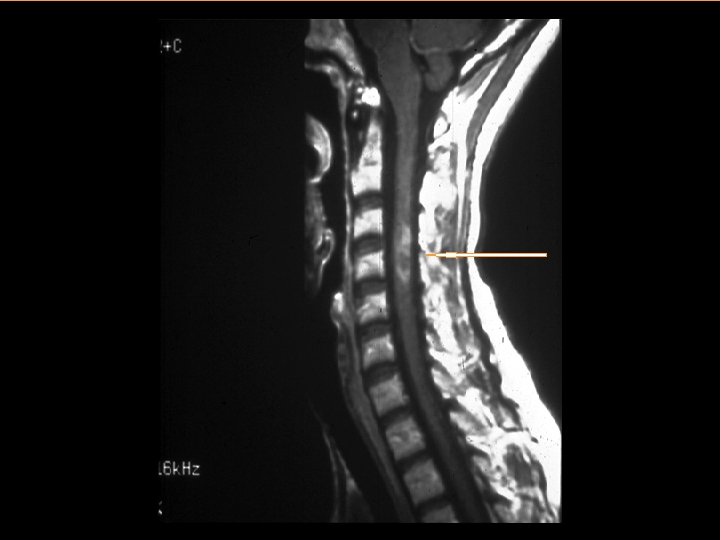

Diagnosing MS • MS is a clinical diagnosis – Signs and symptoms – Medical history • Paraclinical tests provide support – Magnetic resonance imaging – Spinal fluid – Evoked potentials • Diagnostic criteria: – Dissemination in time and space: evidence that damage has occurred in at least two separate areas of the CNS at different points in time – There must be no other explanation

Conventional MRI in MS Clinical Practice FLAIR T 2 BOD* T 1 precontrast T 1 Gd postcontrast Disease Activity† Black Holes† The strongest correlation with progression of disability *Reprinted with permission from Miller DH et al. Magnetic Resonance in Multiple Sclerosis. Cambridge: Cambridge University Press; 1997. †Reprinted with permission from Noseworthy JH et al. N Engl J Med. 2000; 343: 938 -952. Copyright © 2003 Massachusetts Medical Society. All rights reserved.